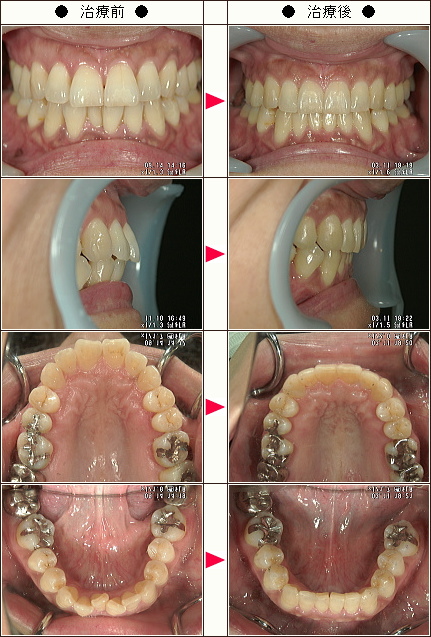

☆歯のデコボコ矯正症例[K.O様 42歳 女性]